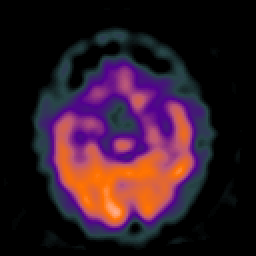

Huntington's Chorea, MR -- Slice #7

[Home][Help][Clinical] Slice 7